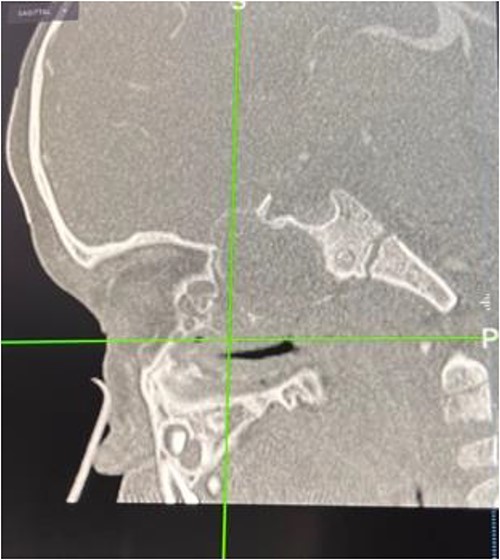

The patient had undergone computed tomography of the paranasal sinuses (CT PNS) and magnetic resonance imaging (MRI) brain with contrast. The MRI showed a heterogeneous mass predominantly occupying the left nasal cavity, left maxillary, and sphenoid sinus, destructing the osseous structure, as well as extending to the medial aspect of the left orbital wall causing minimal proptosis (Figs 1 and 2). Magnetic resonance angiography showed no prominent feeding vessel of the mass. CT PNS demonstrated a heterogenous soft tissue nasal mass extending into the sphenoid wing through the sphenoid sinus, causing skull base erosion but no intracranial invasion.